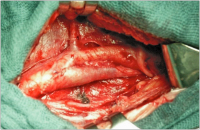

Patchplastik

Abbildung 2: Patchplastik